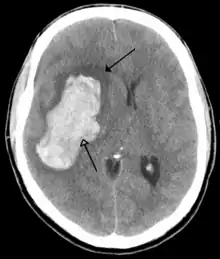

Ictus hemorrágico

Se deben a la rotura de un vaso sanguíneo encefálico debido a un pico hipertensivo o a un aneurisma congénito. Pueden clasificarse en: intraparenquimatosos y hemorragia subaracnoidea.

Las causas más frecuentes en la hemorragia cerebral son la hipertensión arterial y los aneurismas cerebrales.[31]

La hemorragia conduce a ictus a través de dos mecanismos. Por una parte, priva de riego al área cerebral dependiente de esa arteria, pero por otra parte la sangre extravasada ejerce compresión sobre las estructuras cerebrales, incluidos otros vasos sanguíneos, lo que aumenta el área afectada. Ulteriormente, debido a las diferencias de presión osmótica, el hematoma producido atrae líquido plasmático, con lo que aumenta nuevamente el efecto compresivo local. Es por este mecanismo por lo que la valoración de la gravedad y el pronóstico médico de una hemorragia cerebral se demora 24 a 48 horas hasta la total definición del área afectada.